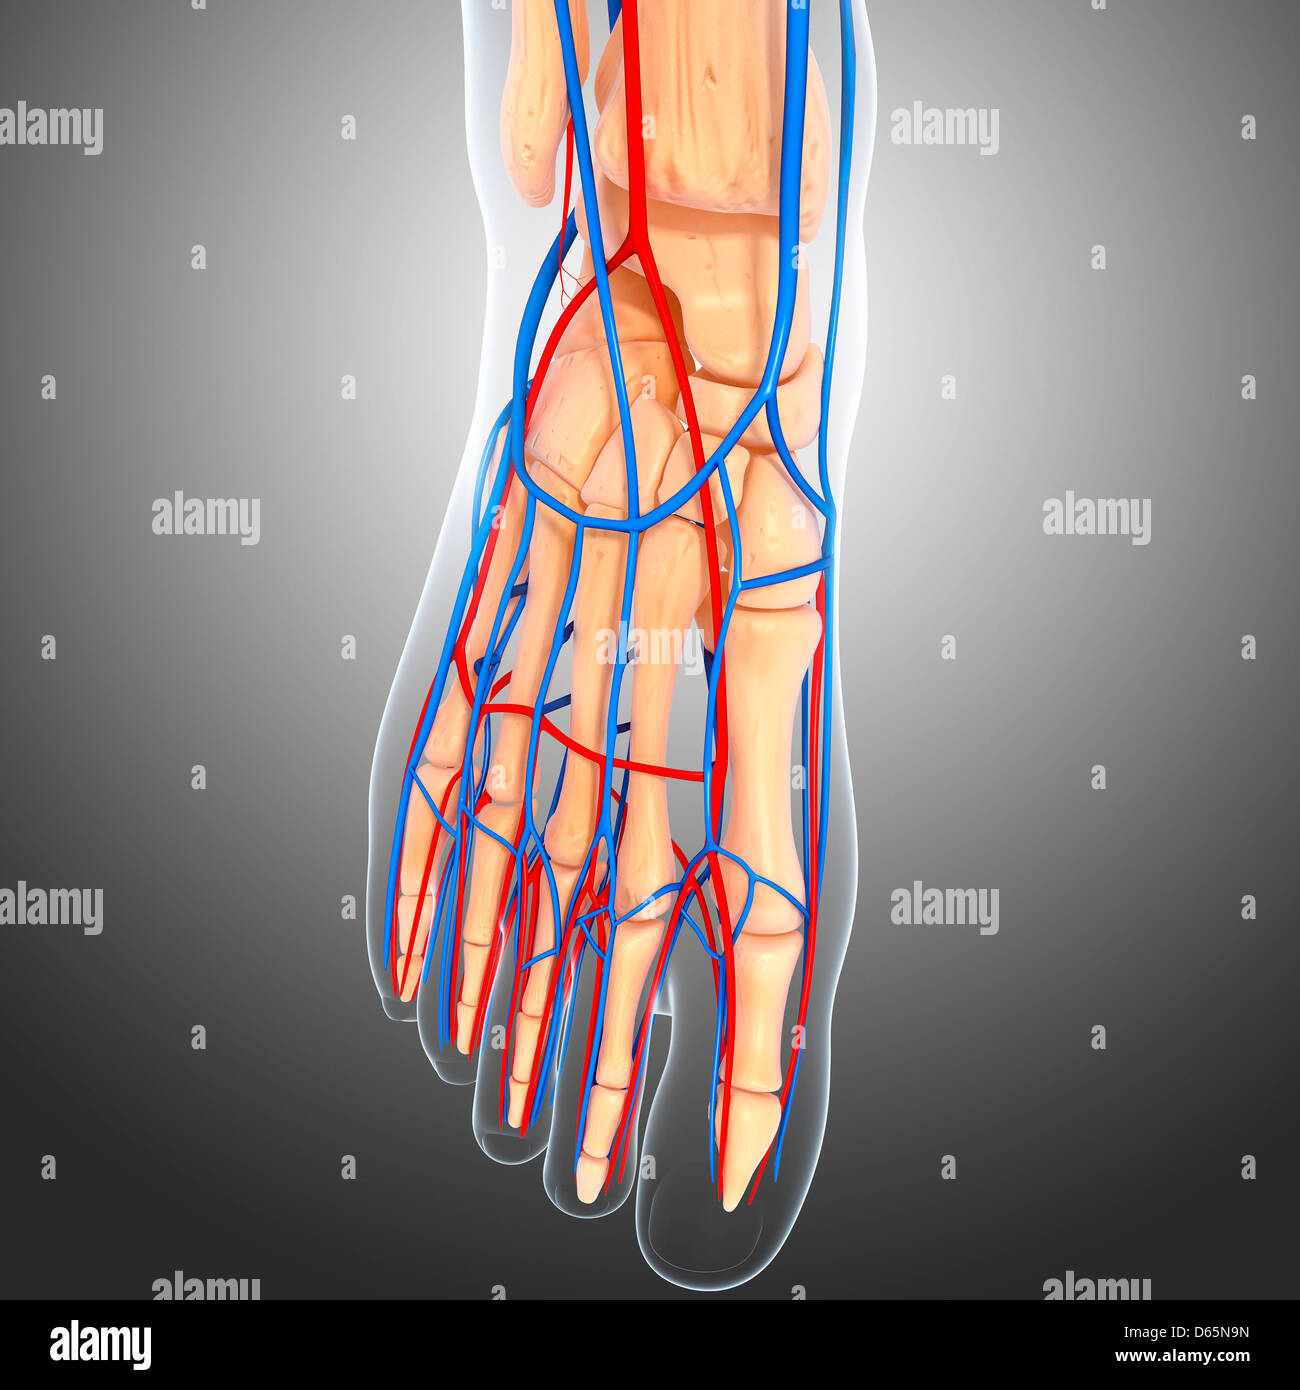

it.dreamstime.comL’anatomia Del Piede Illustrazione Di Stock. Illustrazione Di Linfatico

it.dreamstime.comL’anatomia Del Piede Illustrazione Di Stock. Illustrazione Di Linfatico

it.dreamstime.comanatomie piede anatomia pied arteria

it.dreamstime.comanatomie piede anatomia pied arteria